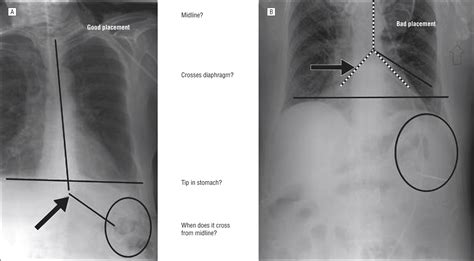

• Tube Advancement: Continue to advance the tube until it reaches the desired location in the small intestine. This can be confirmed using various methods, such as auscultation, pH testing, or X-ray.

• Confirmation of Placement: Use a stethoscope to listen for air insufflation as the tube is advanced. Alternatively, use pH indicator strips to check the pH of the aspirate, which should be alkaline (pH > 6) in the small intestine.

• dobhoff tube placement x ray